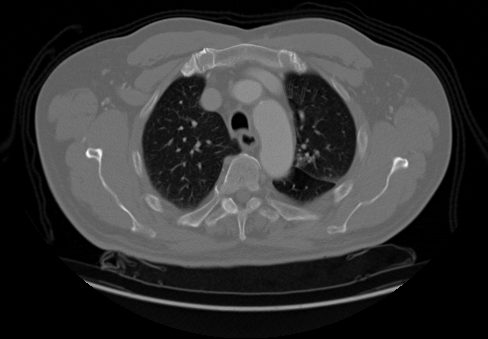

Upload your own CT slice, or click any patient below to instantly see the model classify a real scan.

Try a real scan— click any patient to run inference instantly

INPUT

OUTPUT